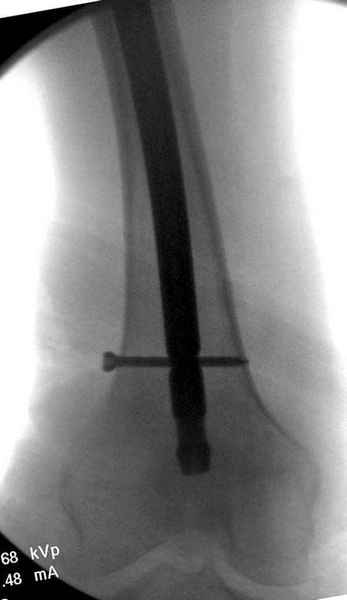

Профилактику дальнейшего раскола неполного перелома шейки провели тремя канюлированными шурупами.

На второй день после выписки упал дома. Снимки приложены. Коллеги рекомендуют удаление шурупа и вытяжение. Что делать?

Наверное речь идет насчет parallel guide из набора. Применяем по возможности всегда, но,

как видно на снимке, не всегда получается

паралельно.

Такие несмещенные переломы обычно для молодых резидентов, и бывают технические неточности, но в этом случае посчитали фиксацию адекватной.